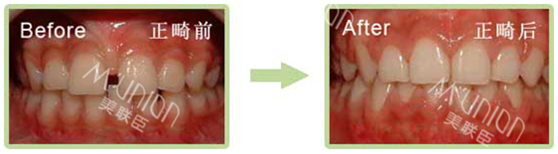

真 人 案 例

传统牙套矫正 18岁的高中生林华1年后效果